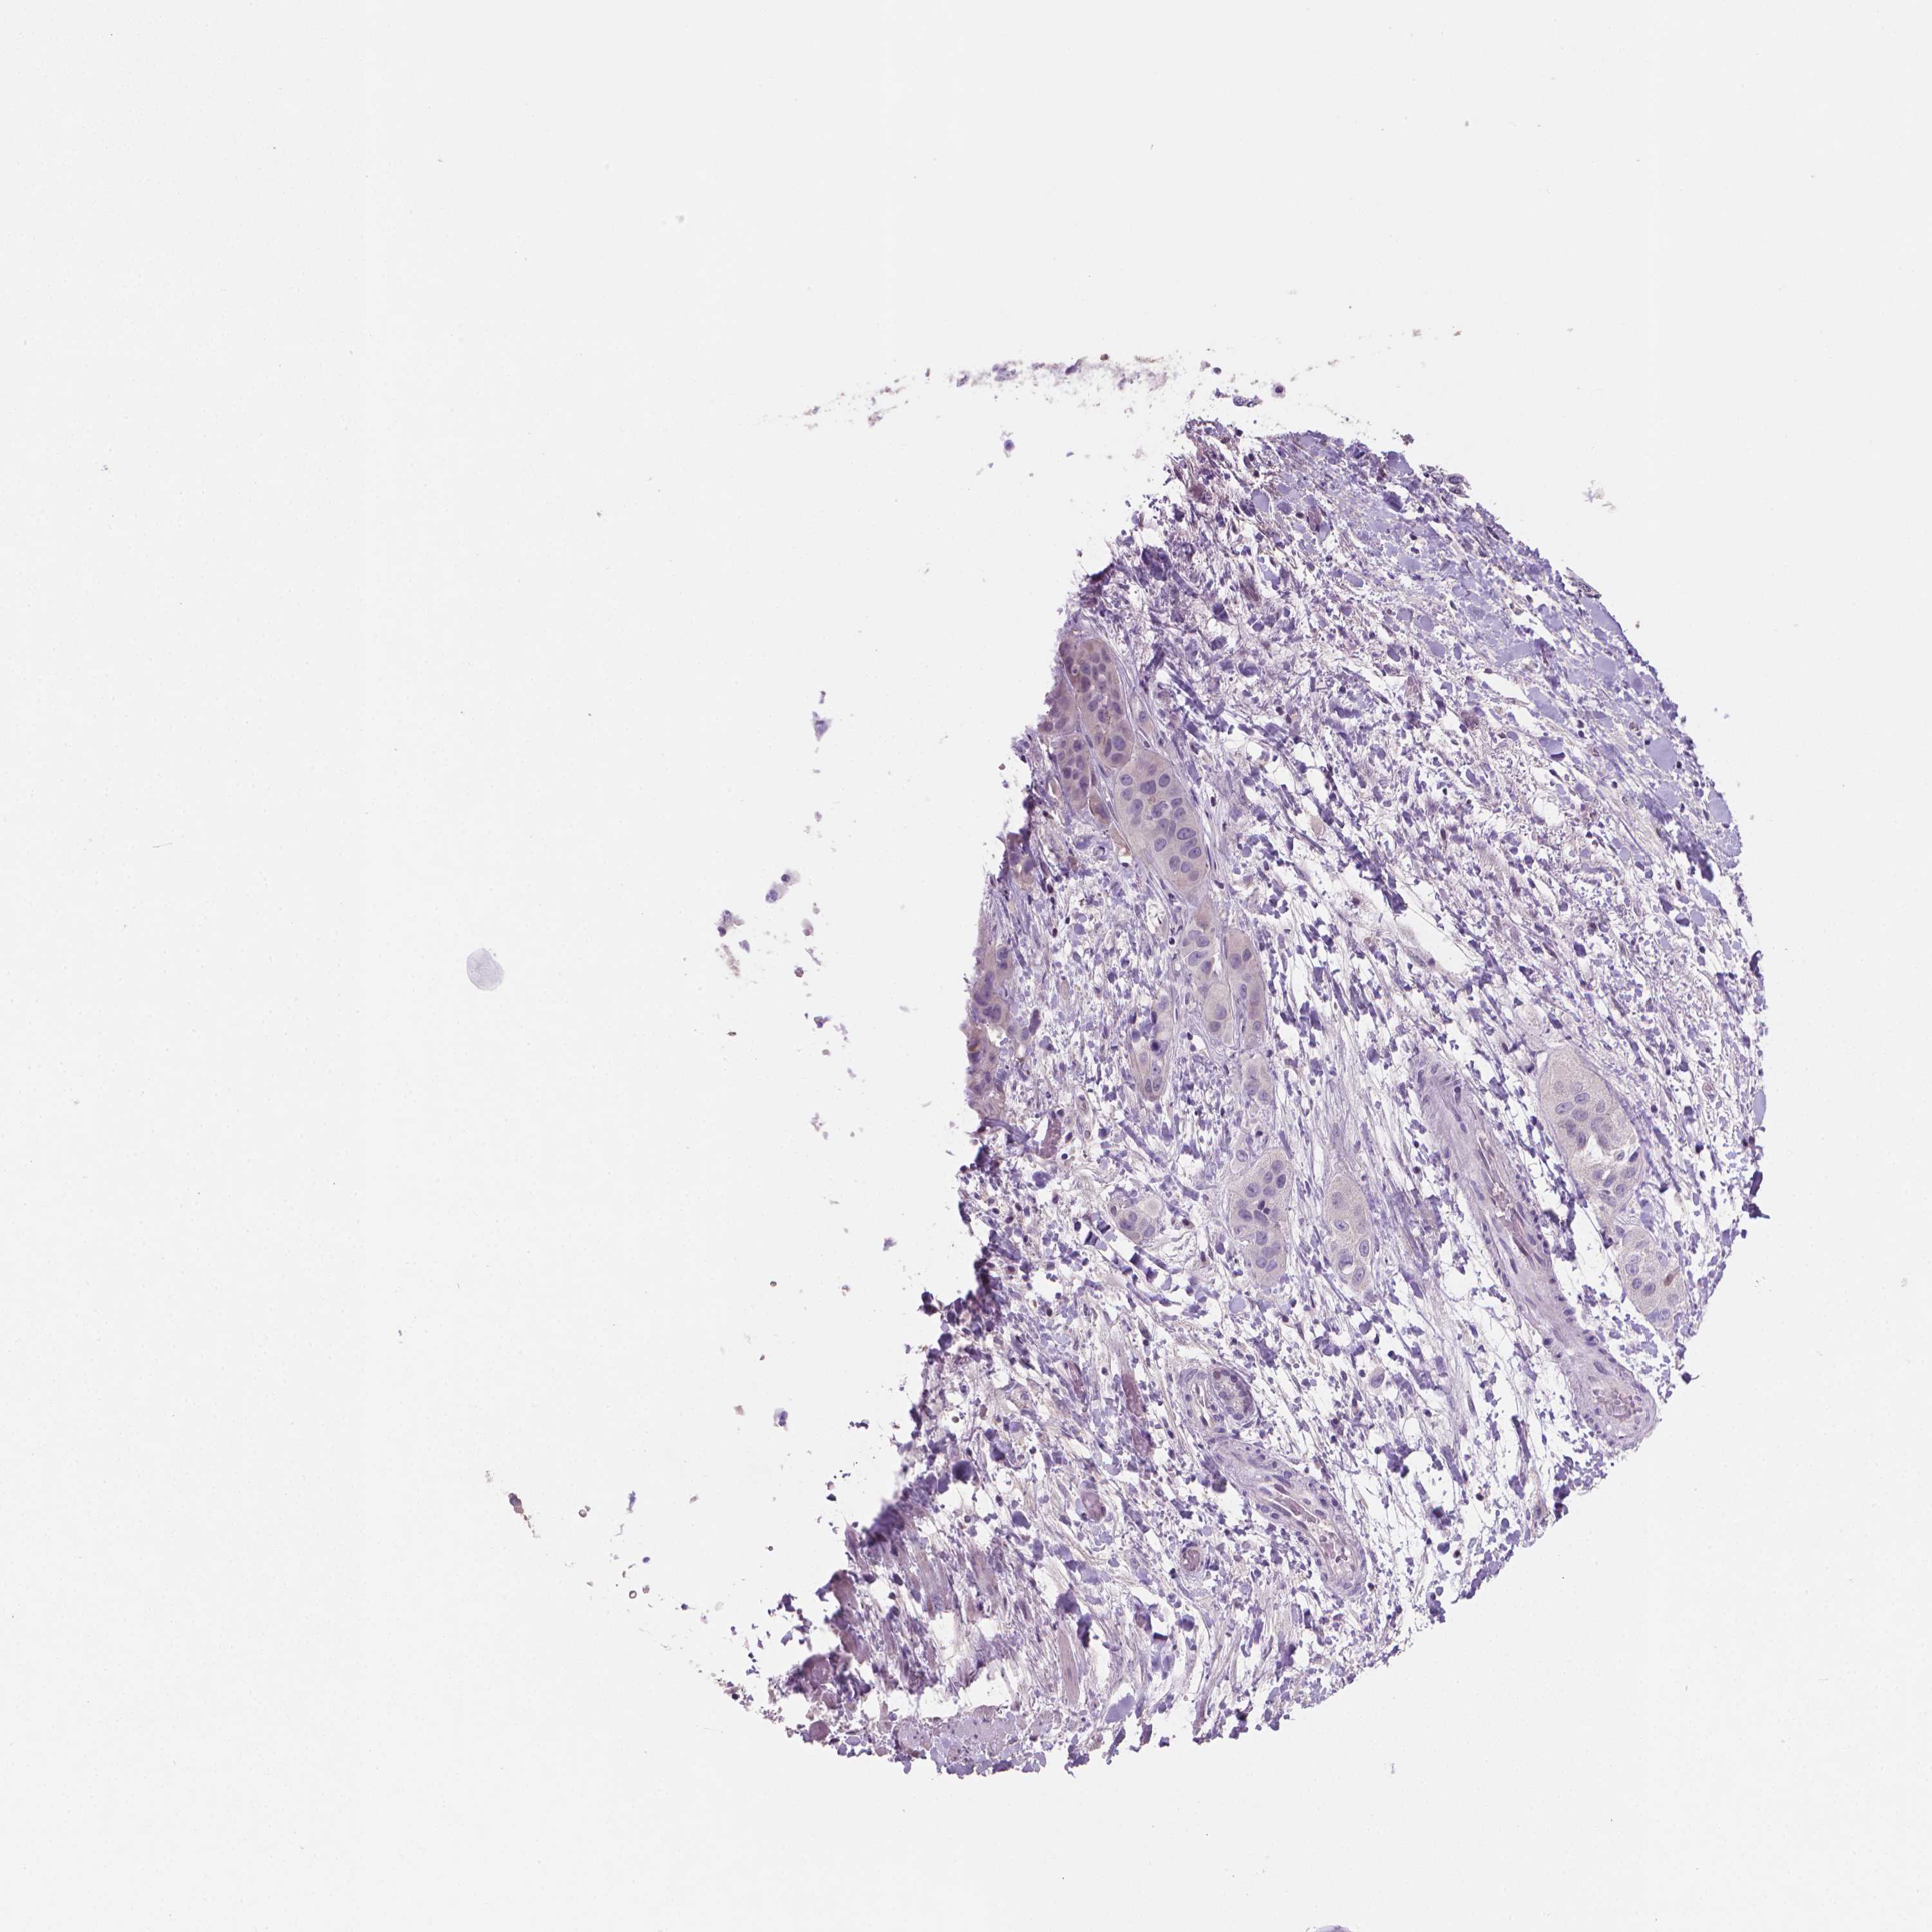

LIVER CANCER - Protein expressioni

A mouse-over function shows sample information and annotation data. Click on an image to view it in a full screen mode. Samples can be filtered based on level of antibody staining by selecting one or several of the following categories: high, medium, low and not detected. The assay and annotation is described here.

Note that samples used for immunohistochemistry by the Human Protein Atlas do not correspond to samples in the TCGA dataset.

Antibody stainingi

Antibody staining in the annotated cell types in the current human tissue is reported as not detected, low, medium, or high, based on conventional immunohistochemistry profiling in selected tissues. This score is based on the combination of the staining intensity and fraction of stained cells.

Each image is clickable and will lead to virtual microscopy that enables deeper exploration of all samples and also displays staining intensity scores, fraction scores and subcellular localization as well as patient and tissue information for each sample.

Antibody HPA023527

Staining

High

Medium

Low

Not detected

Intensity

Strong

Moderate

Weak

Negative

Quantity

>75%

75%-25%

<25%

None

Location

Nuclear

Cytoplasmic/membranous

Cytoplasmic/membranous,nuclear

Carcinoma, Hepatocellular, NOS

Cholangiocarcinoma